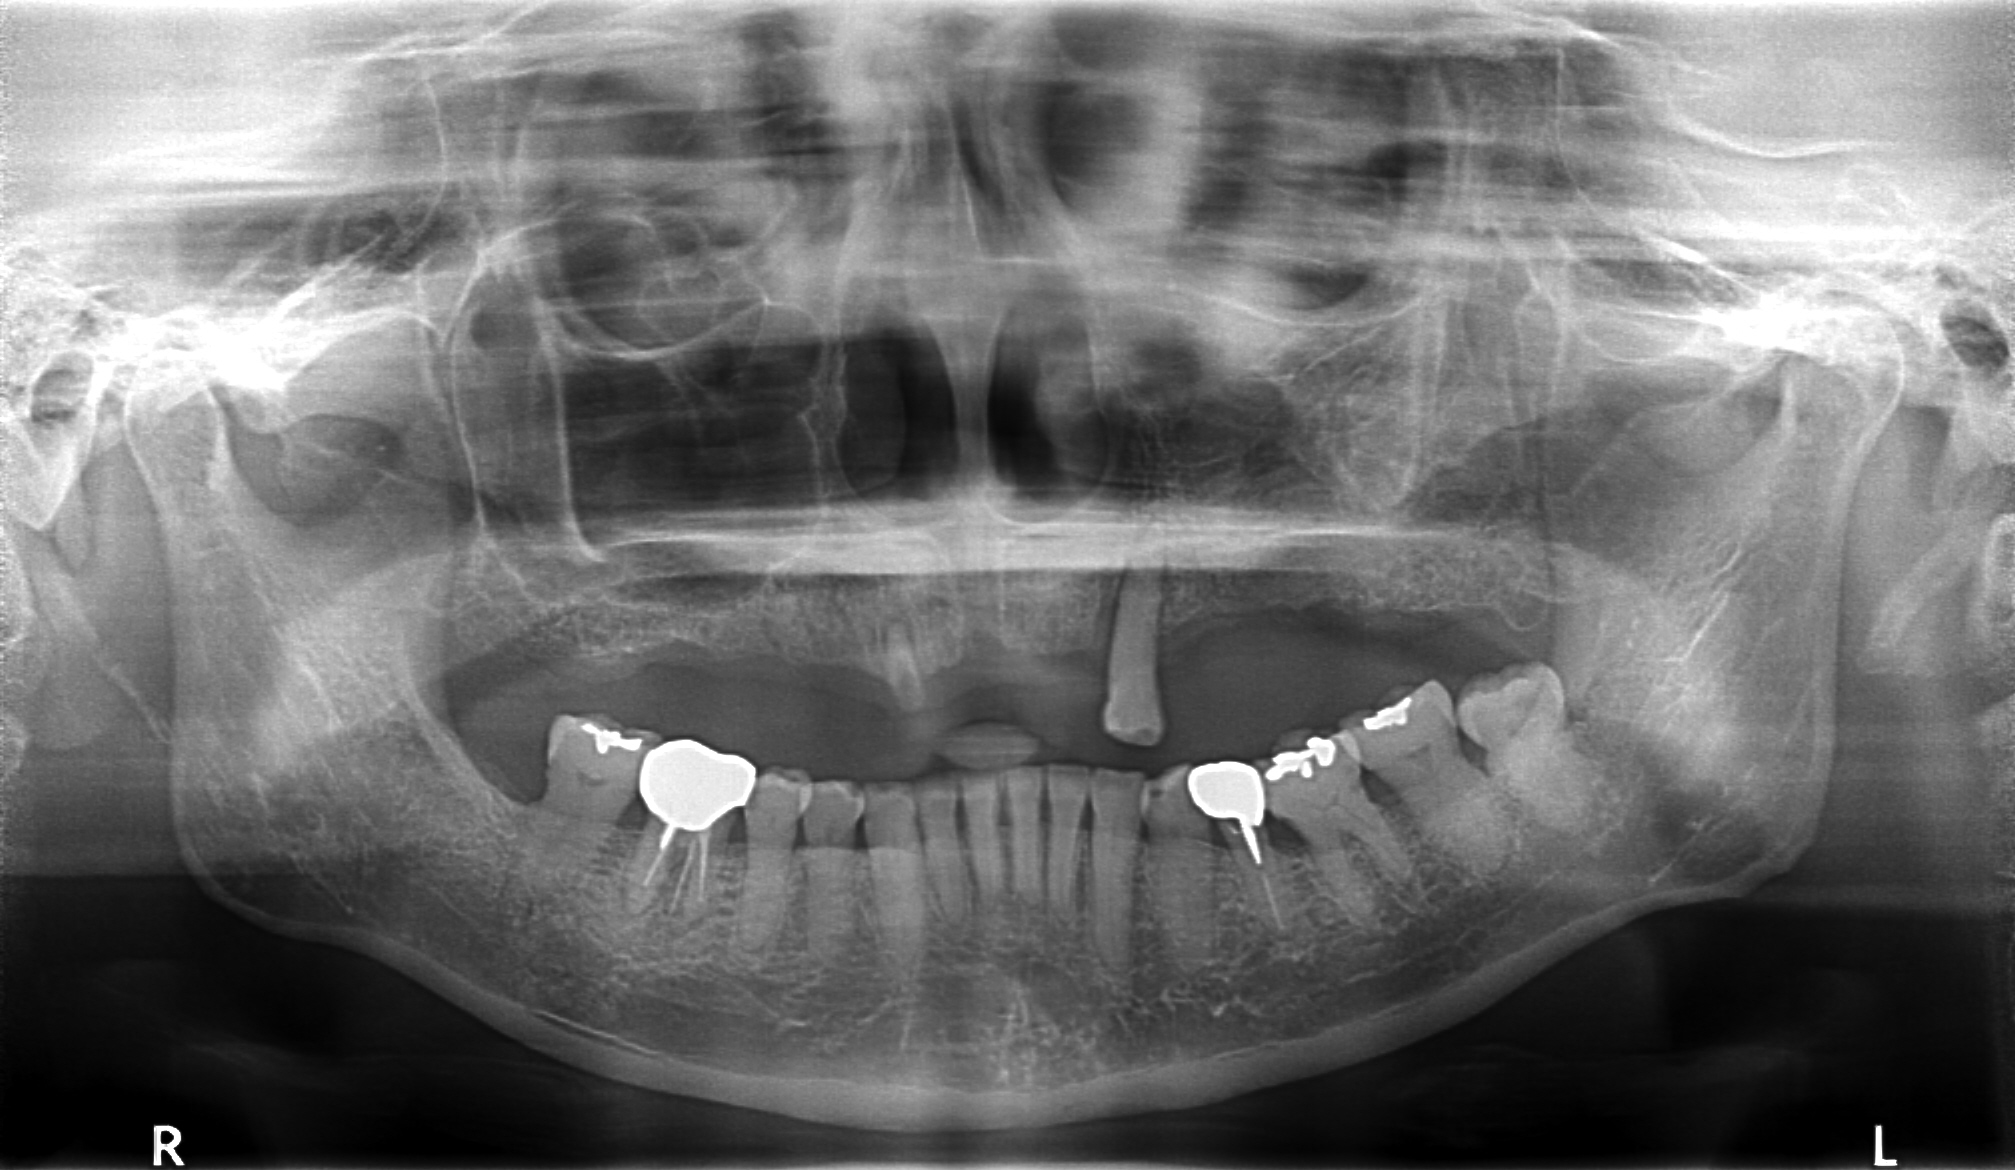

施術前の精密検査

オールオン4を含むインプラント治療は、顎の骨に人工歯根を埋め込むため、施術前の精密な検査が不可欠です。当院では歯科用CTを導入しており、神経や血管の位置、骨の厚みや密度など、従来のレントゲンでは判別できない細部まで立体的に診断します。これにより、より安全かつ正確なオールオン4治療計画を立てることが可能です。

- 主訴

- 上顎入れ歯が辛い、下顎左右の歯が痛い、揺れる

- 処置内容

- 上顎6本(オールオン6) 下顎3本

- 治療費用

- 上顎:約350万円(税込)、下顎:約310万円(税込)仮歯まで5か月)

- 治療期間

- 上顎:1年(仮歯まで8か月)/約10回

下顎:8か月(仮歯まで5か月)/約7回

- リスク

- 上部構造物、仮歯の破折、術後の腫れ(3日)、人工歯根脱落リスクがあります